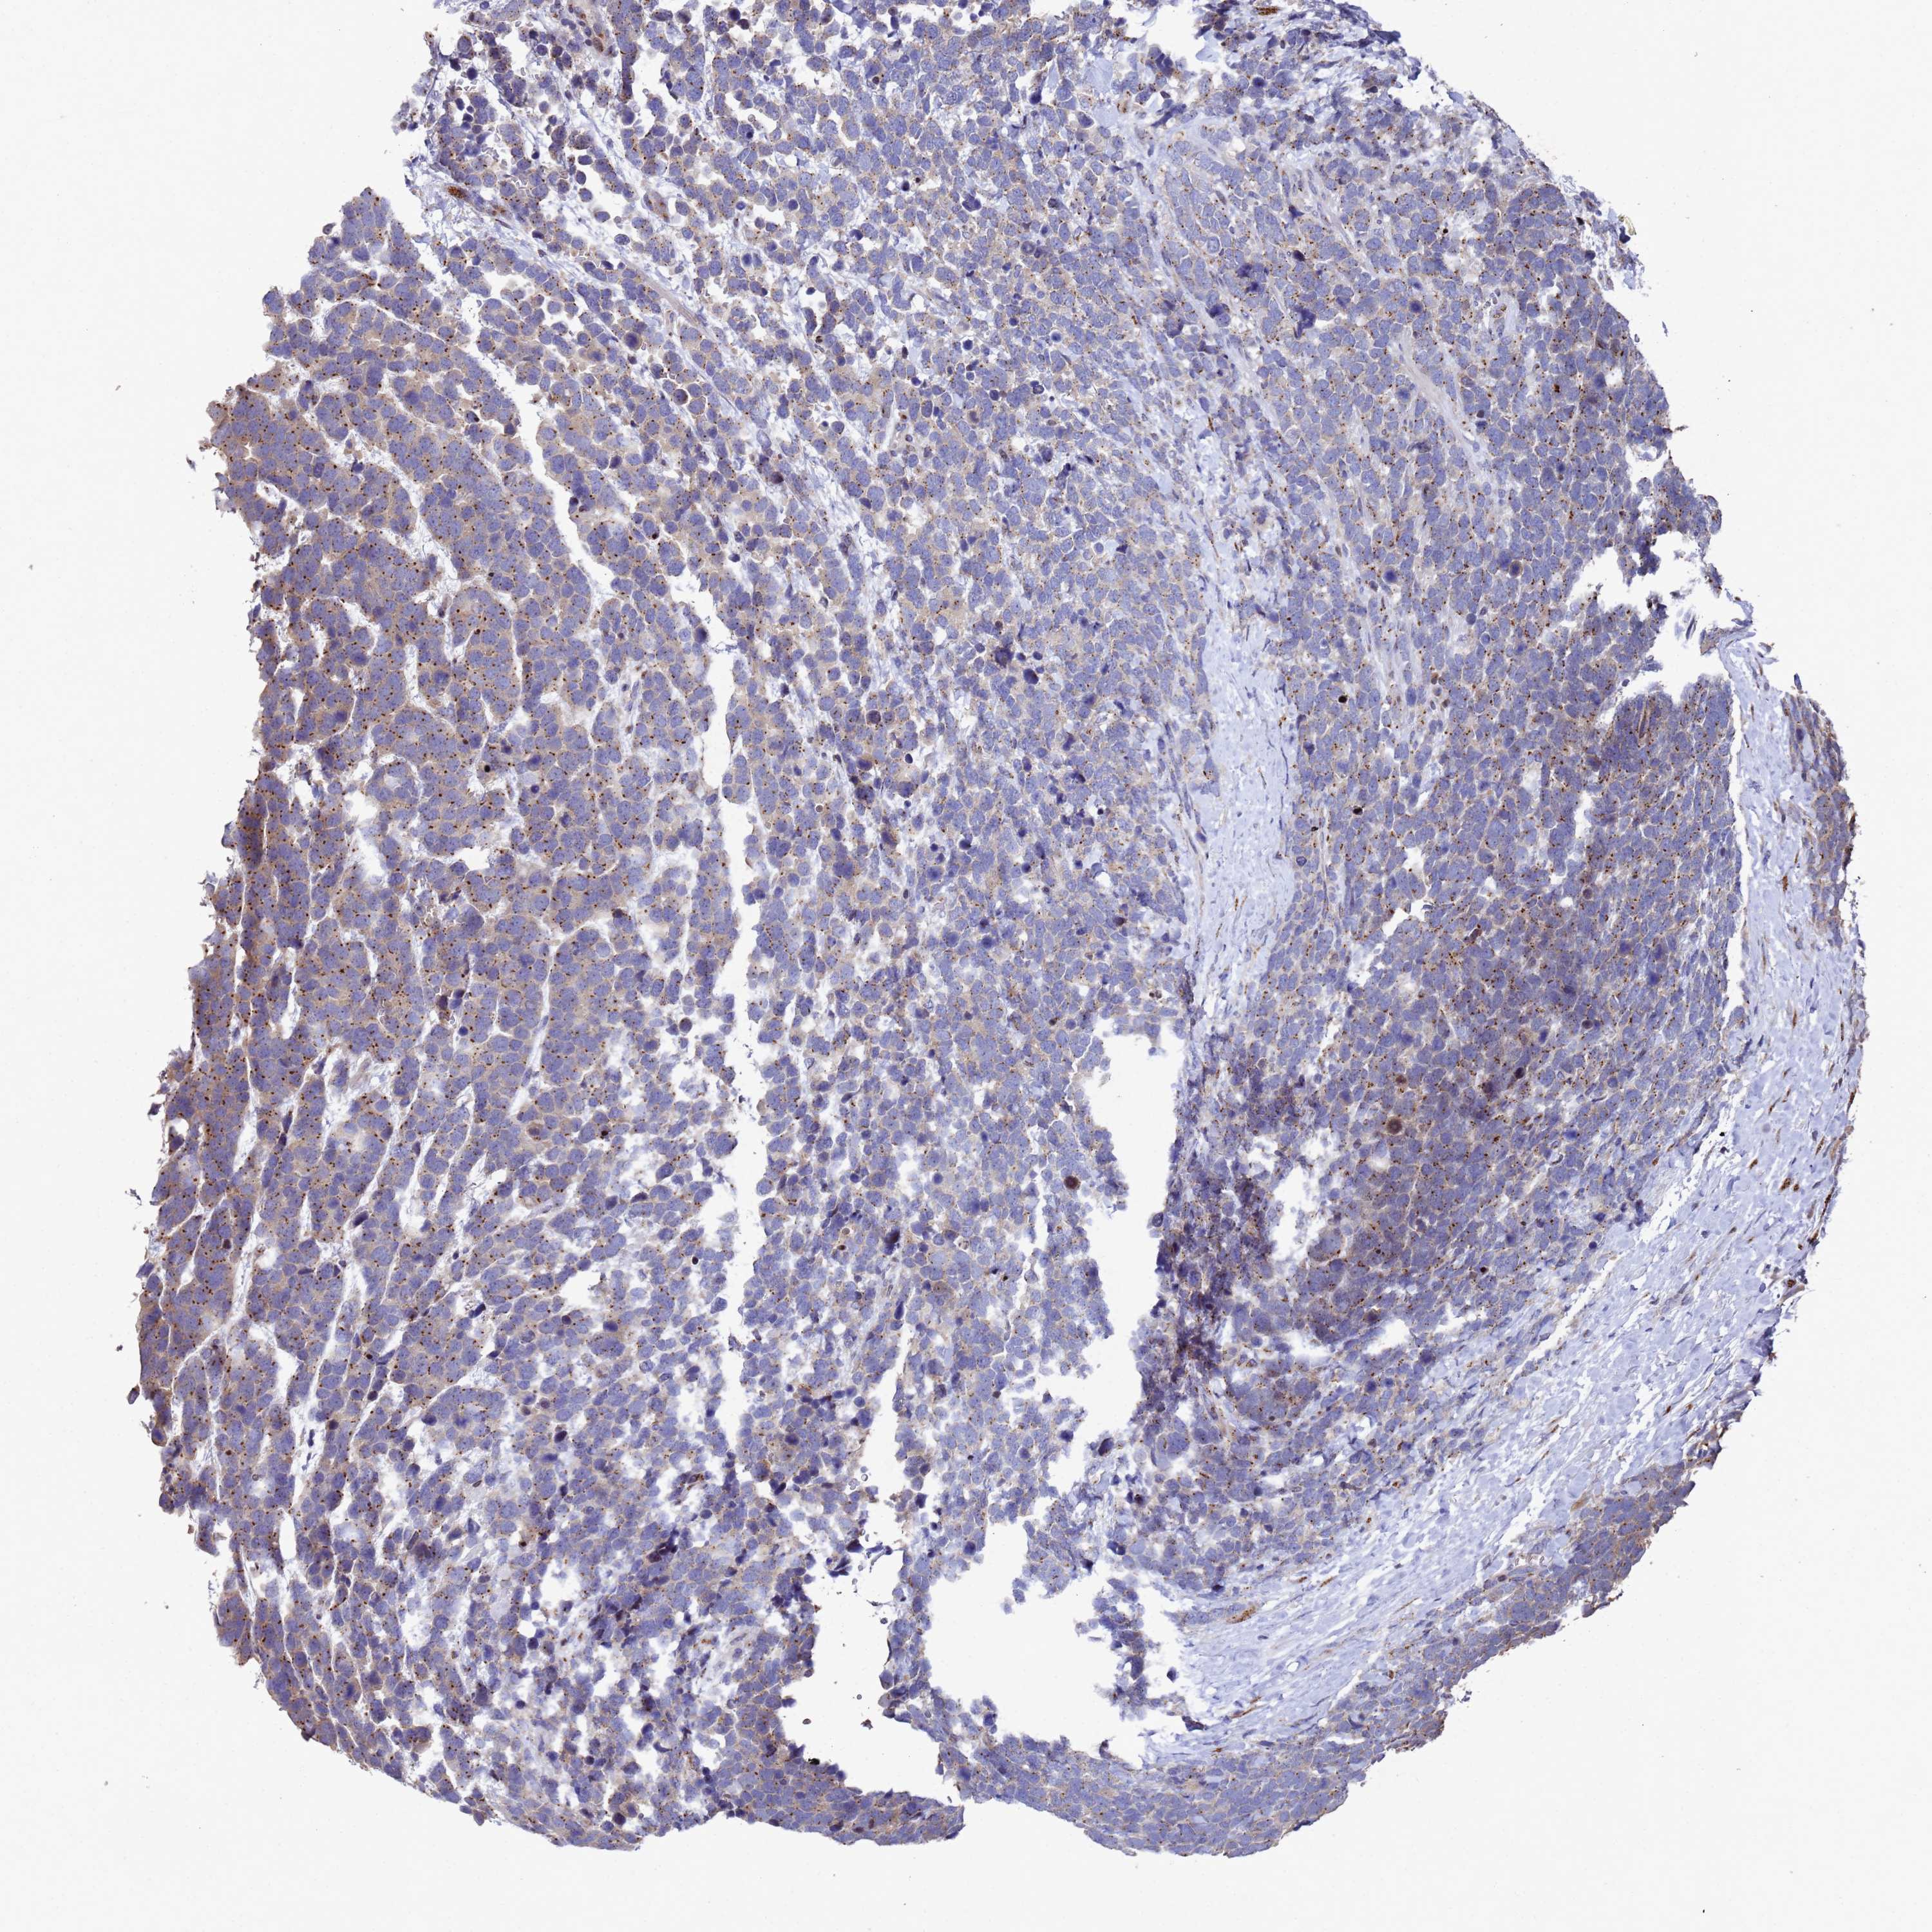

UROTHELIAL CANCER - Protein expressioni

A mouse-over function shows sample information and annotation data. Click on an image to view it in a full screen mode. Samples can be filtered based on level of antibody staining by selecting one or several of the following categories: high, medium, low and not detected. The assay and annotation is described here.

Note that samples used for immunohistochemistry by the Human Protein Atlas do not correspond to samples in the TCGA dataset.

Antibody stainingi

Antibody staining in the annotated cell types in the current human tissue is reported as not detected, low, medium, or high, based on conventional immunohistochemistry profiling in selected tissues. This score is based on the combination of the staining intensity and fraction of stained cells.

Each image is clickable and will lead to virtual microscopy that enables deeper exploration of all samples and also displays staining intensity scores, fraction scores and subcellular localization as well as patient and tissue information for each sample.

Antibody HPA045902

Staining

High

Medium

Low

Not detected

Intensity

Strong

Moderate

Weak

Negative

Quantity

>75%

75%-25%

<25%

None

Location

Nuclear

Cytoplasmic/membranous

Cytoplasmic/membranous,nuclear

Urothelial carcinoma, High grade

Urothelial carcinoma, Low grade